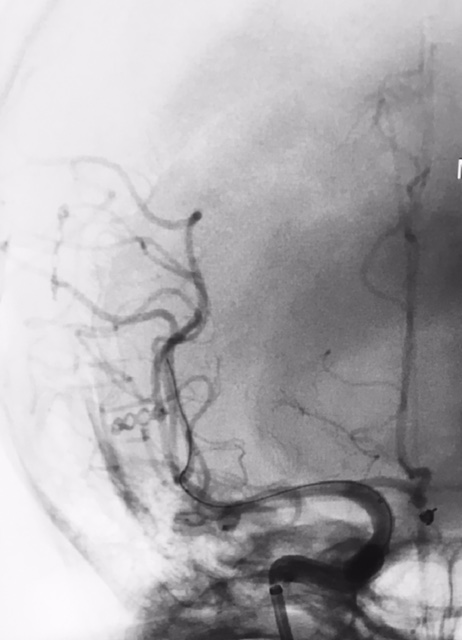

Tratamento de aneurisma cerebral com auxílio de balão duplo lumém e neurostent LEO